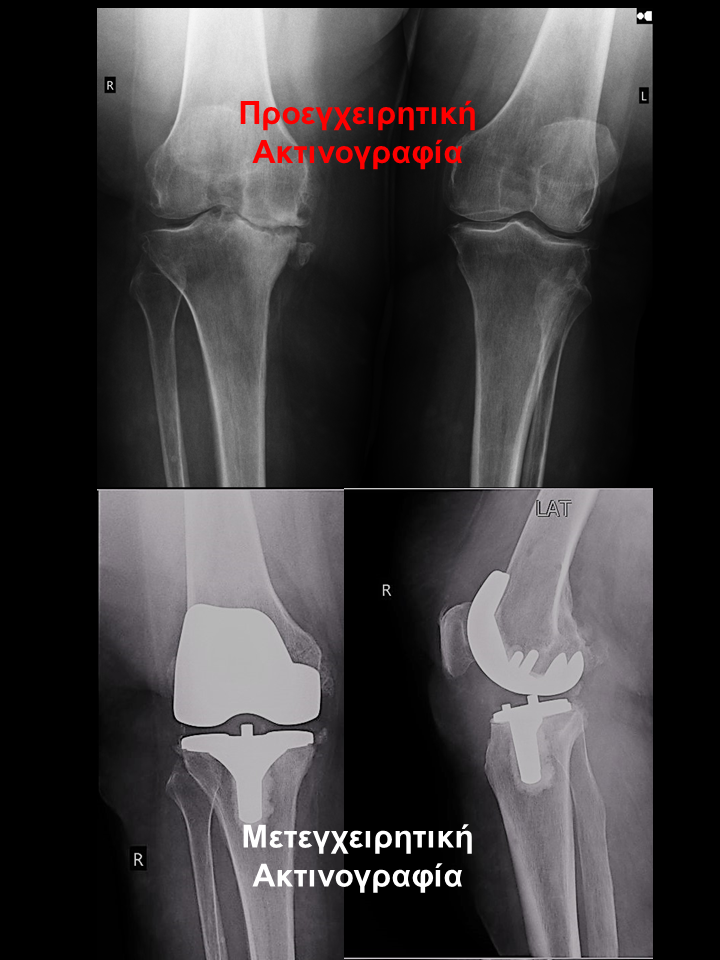

Ασθενής με οστεοαρθρίτιδα δεξιού γόνατος και μεγάλη παραμόρφωση

Ασθενής 74 χρονών με μετατραυματική οστεοαρθρίτιδα και μεγάλη παραμόρφωση. Είχε επιδεινούμενο άλγος δεξιού  γόνατος που την δυσκόλευε στη βάδιση, στο κάθισμα και την αφυπνούσε το βράδυ. Υπεβλήθη σε ρομποτική αρθροπλαστική γόνατος. Χρησιμοποιήθηκε η τεχνική διατήρησης οστού όπου αφαιρέθηκαν λιγότερα χιλιοστά οστού. Ο άξονας από 9.50 αποκαταστάθηκε στις 20 , το έλλειμα έκτασης από 9.50 σε 1.50  και η κάμψη στις 1170. Η ασθενής έλαβε εξιτήριο τη δεύτερη ημέρα και βαδίζει πλέον χωρίς καμία ενόχληση.